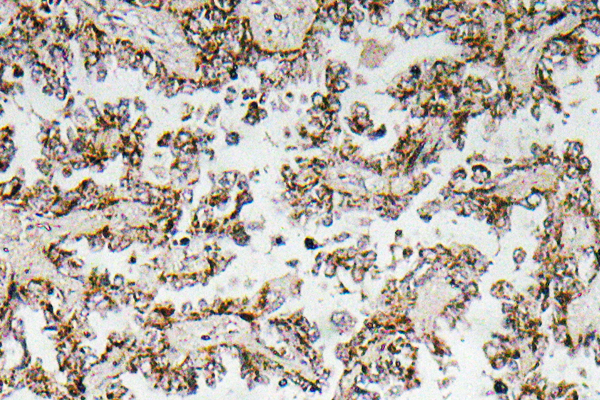

IHC image of CSB-PA005963OA01HU diluted at 1:100 and staining in paraffin-embedded human prostate cancer performed on a Leica BondTM system. After dewaxing and hydration, antigen retrieval was mediated by high pressure in a citrate buffer (pH 6.0). Section was blocked with 10% normal goat serum 30min at RT. Then primary antibody (1% BSA) was incubated at 4°C overnight. The primary is detected by a biotinylated secondary antibody and visualized using an HRP conjugated SP system.